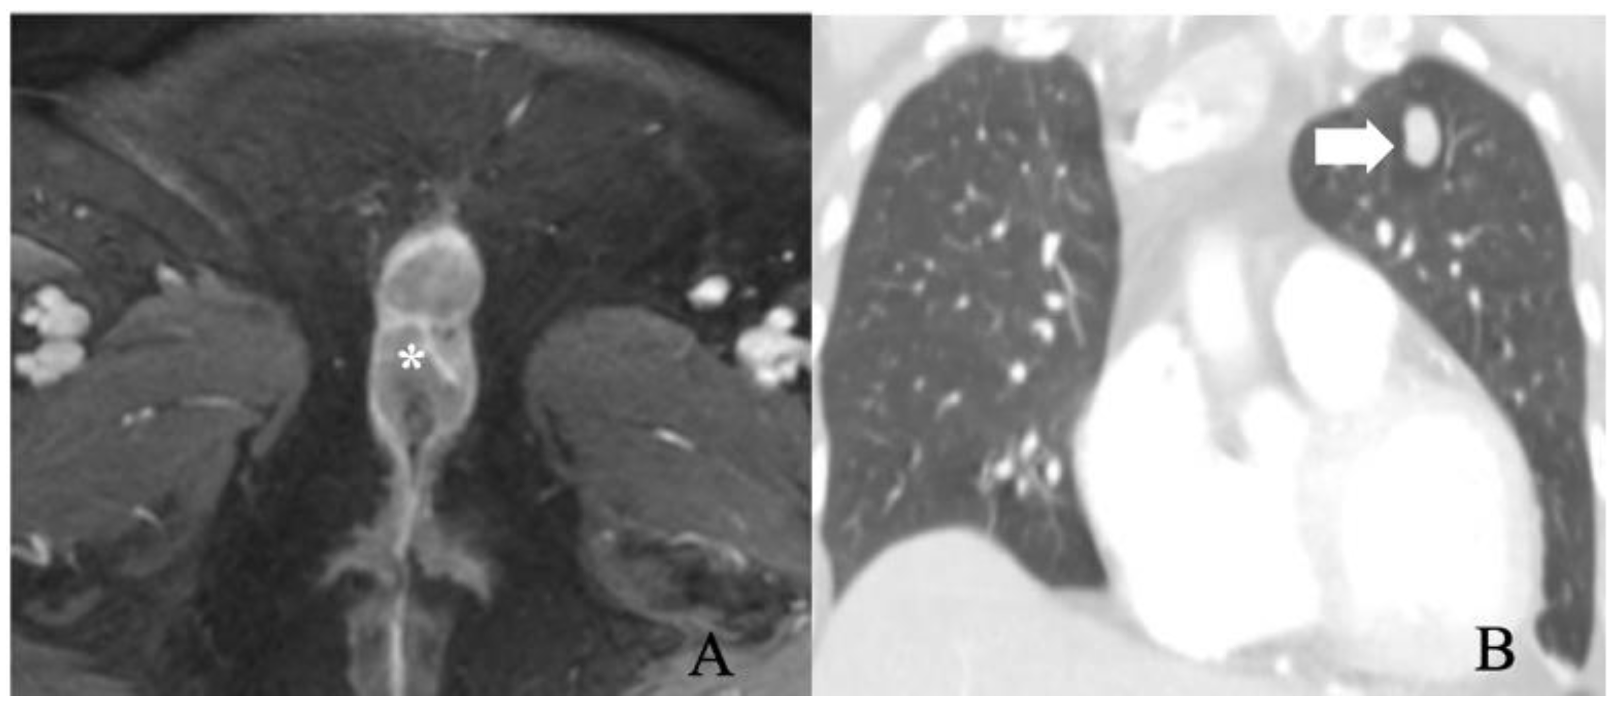

5.4. Stage IV

6. Treatment